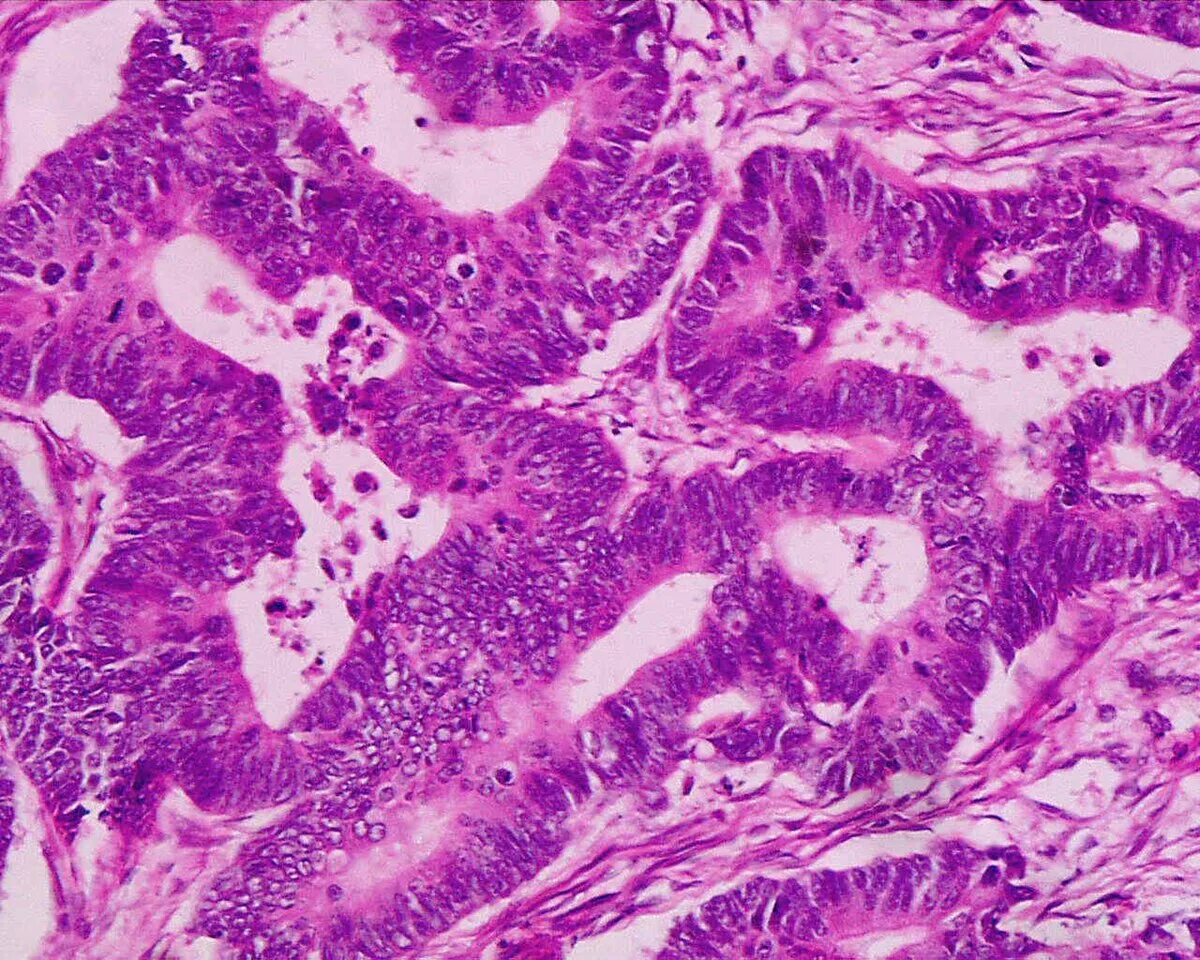

Аденокарцинома легких 4 стадия прогноз